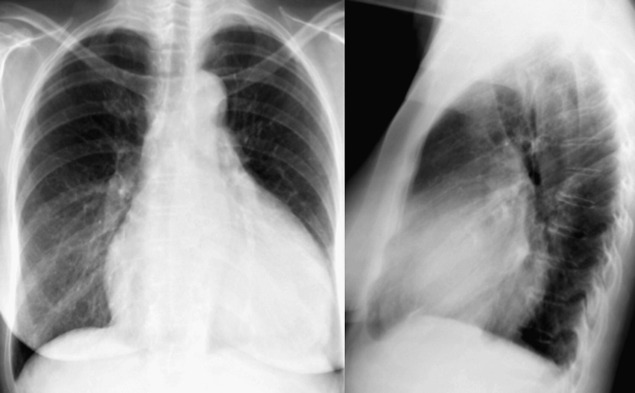

A pericardial effusion ( Figs. 16-1 to 16-15 ) is often suggested on the frontal chest radiograph by a smoothly distended, “flasklike” CPS. More than 500 mL of fluid must be present before the change in the CPS is fairly obvious. A flasklike appearance may be caused by myocardial disease as well; scrutiny of the hilar vessels may distinguish the two. In the presence of pericardial effusion, the hilar vessels are covered (the pericardium runs up onto them and obscures them). In the presence of myocardial disease, the hilar vessels are unusually prominent as they are distended under higher than usual pressure.

In a minority of patients with pericardial effusion, on the lateral radiograph, a stripe of radiolucent epicardial fat, a “fat line,” may be visible anteriorly, suggesting fluid in the pericardial space. A stripe greater than 2 mm is abnormal. This “pericardial stripe sign” is more easily seen in adults than children (more fat!).